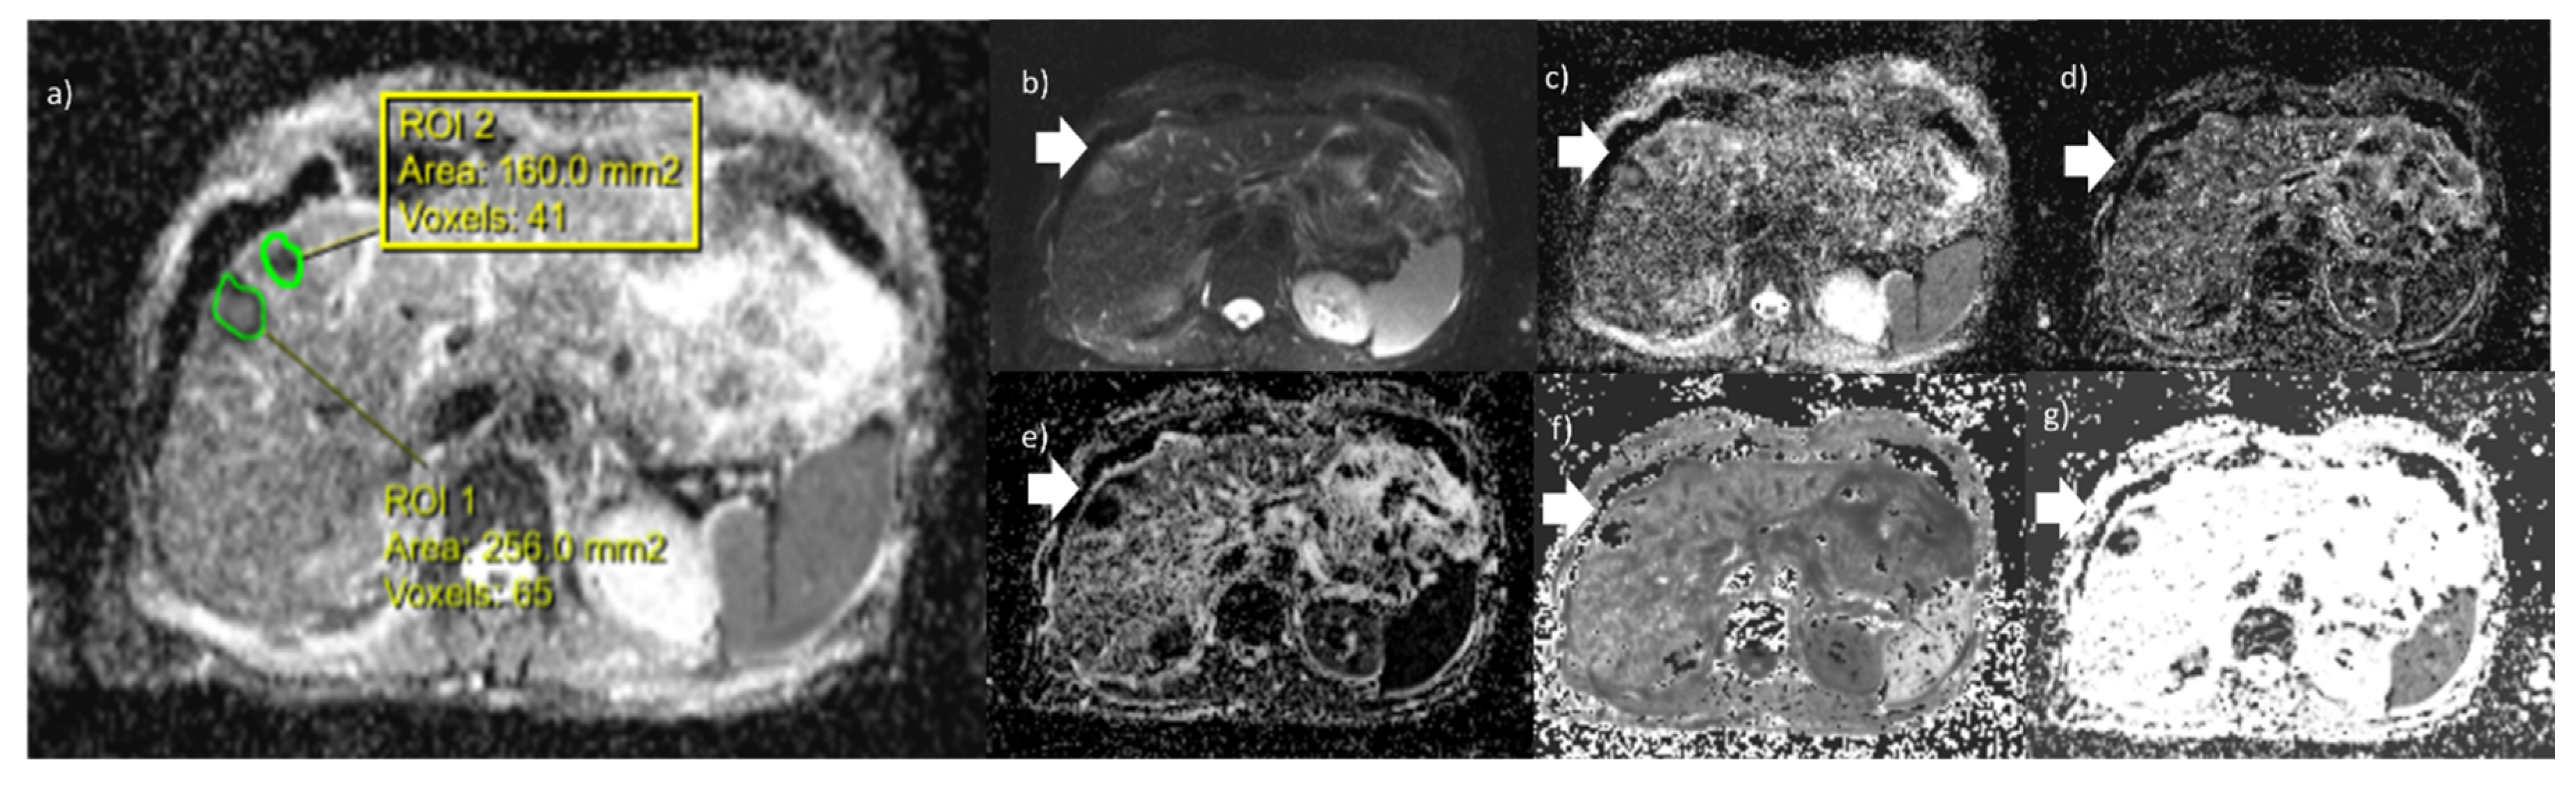

DWI Features